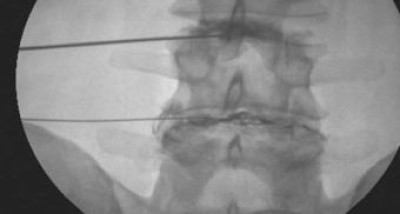

Agujas Colocadas para Bloqueo Transformainal en Cuello

Discografía L3, L4 y L4, L5 AP